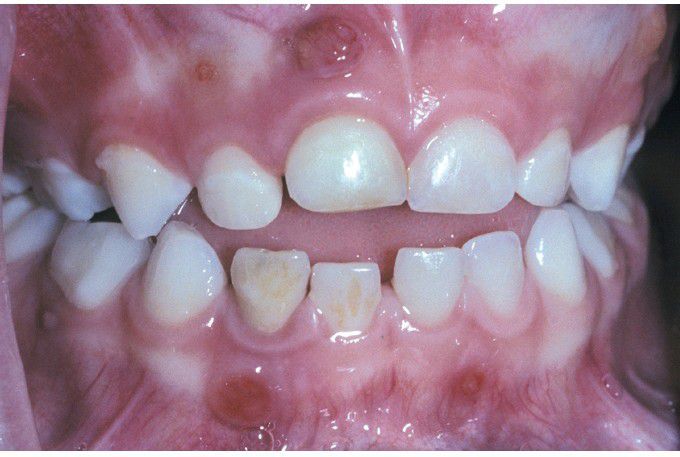

Vitamin D–Resistant Rickets.

This patient exhibits multiple nonvital teeth with associated parulides. This arose in the absence of caries or trauma.